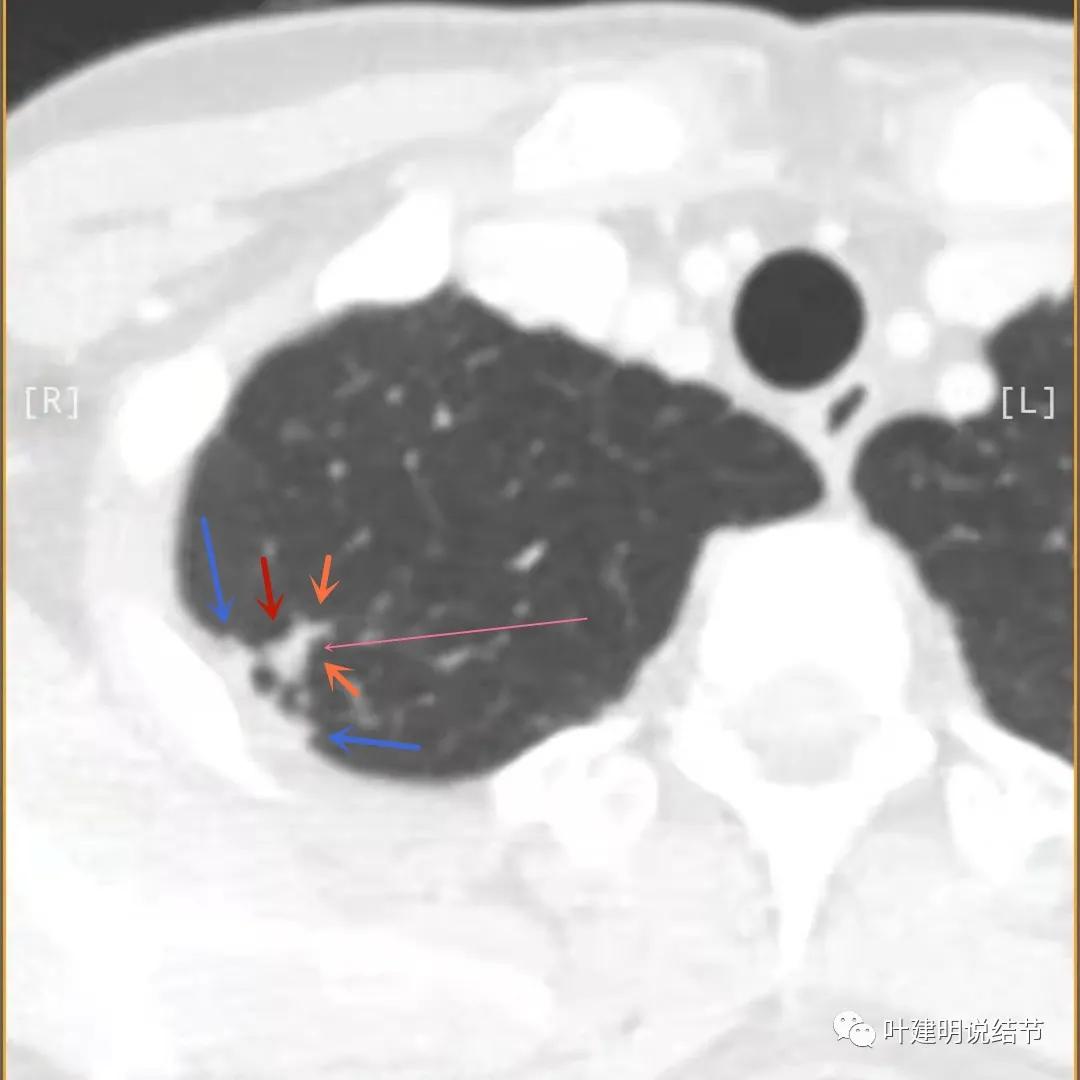

下面是今年复查的平扫片子,来看看有什么变化:

病灶邻近胸膜异常增厚(蓝色箭头)

有卫星灶(绿色箭头),邻近胸膜明显增厚,且模糊,边不清

邻近胸膜增厚

主病灶此层面似三角形,邻近胸膜增厚(蓝色箭头),结节实性部分密度较高(粉色箭头),边缘显模糊(砖色箭头)

上图与恶性较为符合,空洞性病灶,壁厚薄不均,增厚部分还凹凸不平(细红色箭头所指)

上图磨玻璃部分密度过低,且与正常肺组织界限模糊(砖色箭头),粉色箭头示囊壁密度过高的点状,蓝色箭头示邻近胸膜处的增厚

上图也像恶性,但整个囊壁的密度感觉过高了点,边缘磨玻璃淡、散且模糊,邻近胸膜有增厚

上图病灶的边相对比较光,没有毛刺征,邻近胸膜增厚

上图病灶边缘比较平直,没有膨胀性(桔色箭头),旁边的磨玻璃影淡且界限不清,邻近胸膜增厚。

再看影像印象:病灶较1年前有所进展,部分层面像恶性,囊壁厚薄不均,内面有小突起。但邻近胸膜增厚,旁边的磨玻璃部分散且淡,边界不清,实性部分边相对较光,囊壁有点状过高密度。良性可能性大些,恶性不能除外。